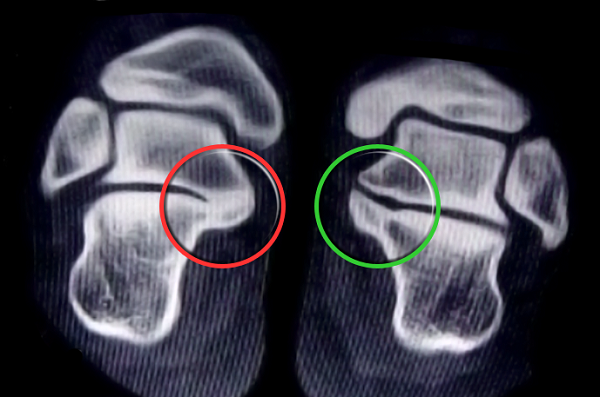

A tomografia é o melhor exame para diagnosticar a coalizão tarsal. Ela permite um melhor entendimento do tamanho e da forma da fusão entre os ossos.

Coalizão Talocalcaneana (vermelho) - Normal (verde)

A ressonância magnética é útil para coalizões ainda não calcificadas, crianças menores de 10 anos ou coalizões fibrosas ou cartilaginosas discretas.